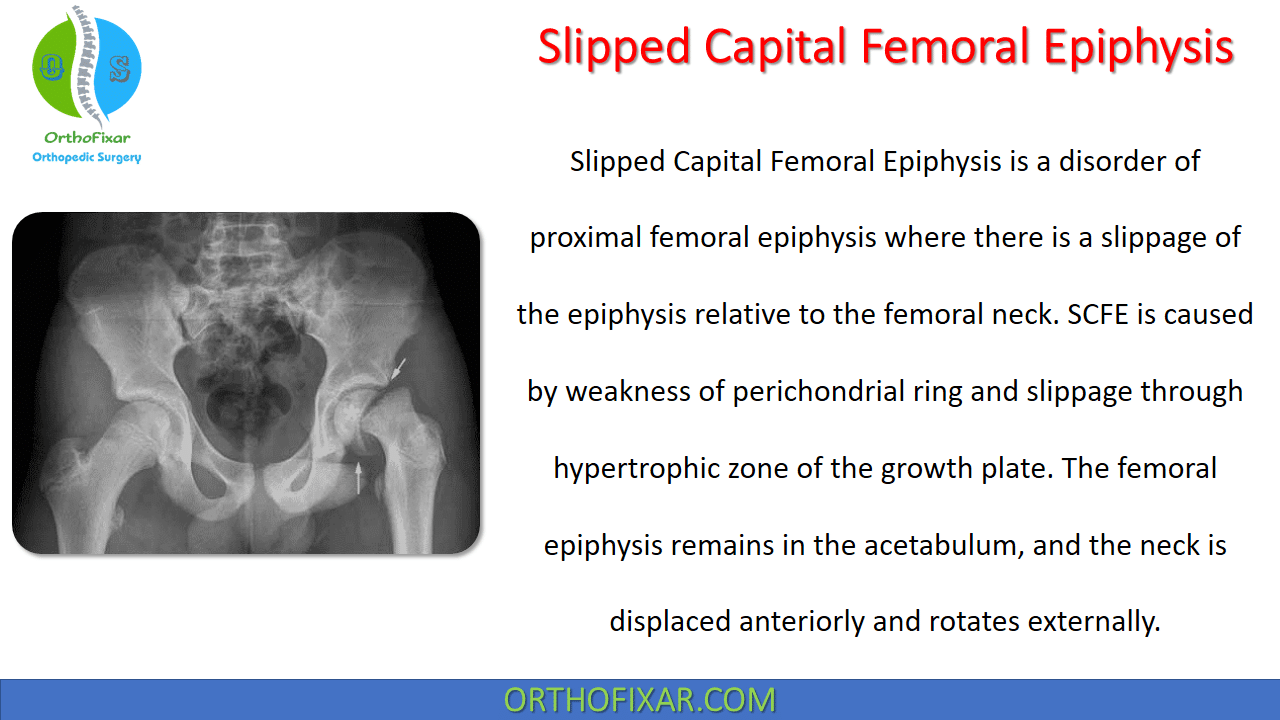

Slipped Capital Femoral Epiphysis

epiphysis slipped femoral

Slipped capital femoral epiphysis (scfe). Slipped capital femoral epiphysis (scfe). Slipped capital femoral epiphysis radiology